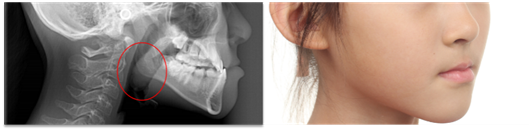

腺样体面容

除腺样体肥大引起的腺样体面容外,当扁桃体肥大时,患儿倾向于下颌前伸以获得足够通气,从而造成地包天面容。